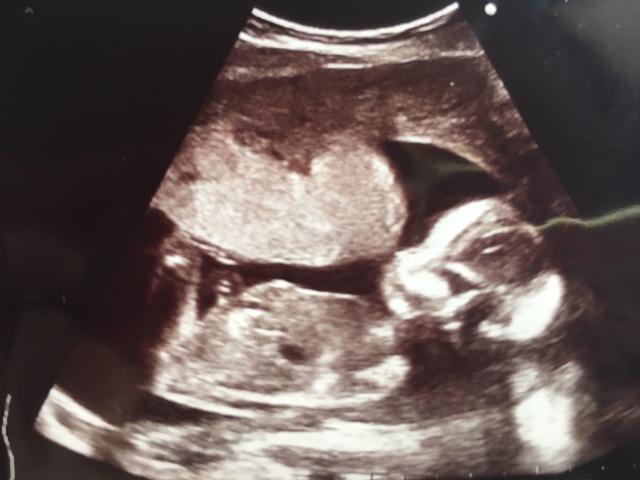

16週0日(16w0d・女の子)|aiscream さん(27歳)

エコー写真撮影時のエピソード:

初めての妊娠。 どんどん大きくなる赤ちゃんの姿を楽しみに 待ちに待った健診 (o^^o)

元気な心臓の音を聞かせてくれて、 エコーも終盤になった頃 やっほー♪またねー♪ と言わんばかりに赤ちゃんが右手を上げて手を振ってくれたときの1枚です♡♡

※こちらのエコー写真は第1回「コズレエコー(超音波)写真コンテスト」の受賞作です!